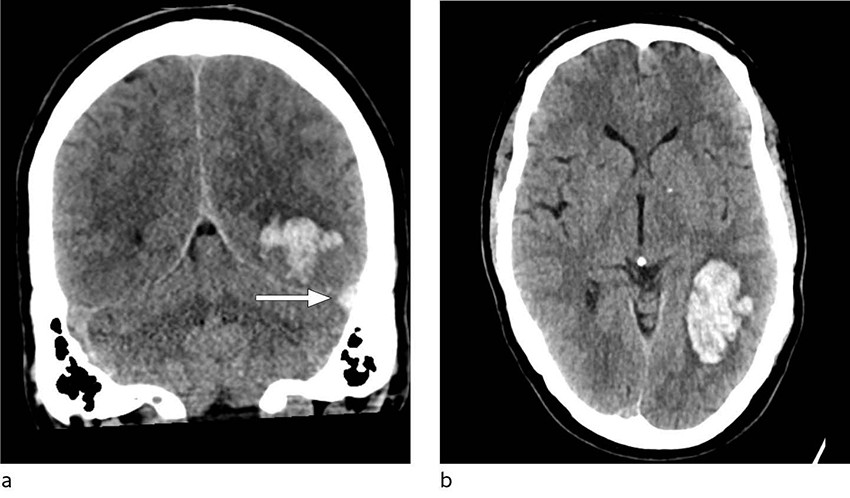

Ved innkomst fremsto han forvirret, søvnig og med afasi. CT caput avdekket intracerebral blødning i venstre temporallapp, og pasienten ble overflyttet til universitetssykehus for observasjon. Ved ankomst der var pasienten våken, men desorientert og hadde afasi uten andre fokalnevrologiske utfall. Han skåret 4 poeng på National Institutes of Health Stroke Scale, forenlig med et mindre hjerneslag. Kontroll-CT caput uten kontrast viste uendret størrelse av hjerneblødningen, og det ble reist mistanke om hemoragisk venøst infarkt grunnet tegn til cerebral venetrombose (figur 1). Supplerende CT-venografi viste manglende kontrastfylning av sinus transversus og sinus sigmoideus på venstre side, som bekreftet diagnosen (figur 2). Det ble samme dag startet behandling med lavmolekylært heparin i form av dalteparin 100 IE/kg to ganger daglig.